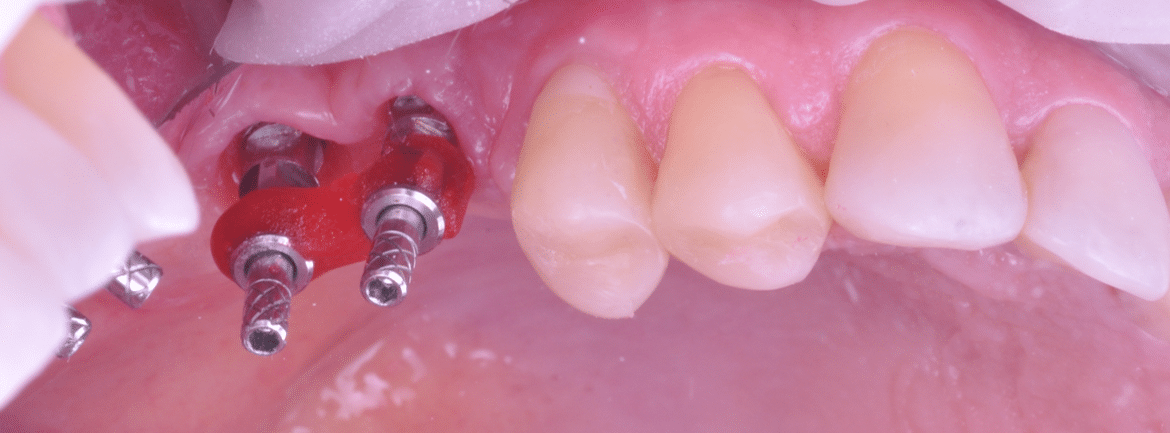

Împreună cu pacientul, am optat pentru inserarea implantelor cu ajutorul ghidului chirurgical pentru a plasa implantul în poziția protetică ideală și pentru a permite realizarea coroanelor insurubate pe implant. A fost efectuată scanarea digitală a arcadelor și a ocluziei pacientului, iar împreună cu tehnicianul radiolog de la DigiRay a fost suprapus fișierul .stl al amprentei digitale peste fișierul .dcm de la CBCT, utilizând software-ul 3Shape.

S-a planificat individual poziția și axul de inserție al fiecărui implant.

Doar astfel putem crea profilul de emergență corect al coroanei dentare, ceea ce permite conformarea papilei și a sulcusului.